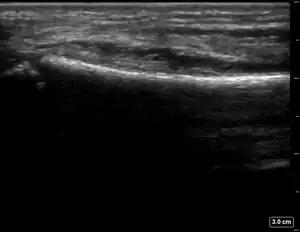

| 2 | ![]() |

![]() |